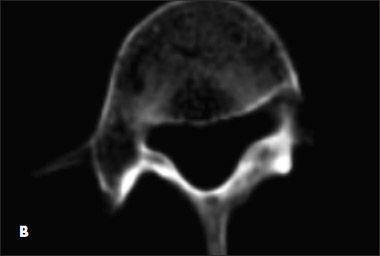

The patient had mild leukocytosis, anemia, and corrected calcium level of 11 mg/dL. Cerebrospinal fluid analysis yielded normal results. A brain CT scan showed multiple lytic lesions in the calvarium, with the largest in the left parietal bone (A). Abdominal CT revealed hepatosplenomegaly with low-attenuation lesions and scattered lucencies throughout the vertebral bodies (B).

Kaposi sarcoma or Mycobacterium haemophilum infection can lead to lytic lesions in bones.5,6 However, MAIC infection as a cause of lytic bone lesions has not been described. Further studies are needed to verify whether lytic lesions explain hypercalcemia in disseminated MAIC infection in persons with HIV/AIDS in the absence of elevated vitamin D levels.